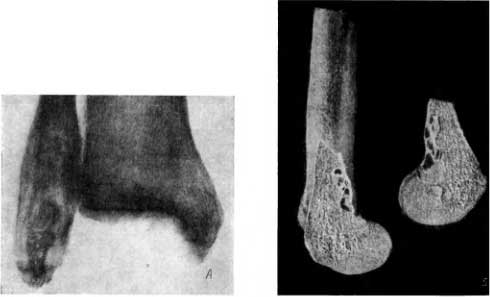

В погребении в Саркеле была найдена малоберцовая кость с резко деформированной лодыжкой, размеры которой были почти вдвое увеличены. Рентгенологическое исследование позволило поставить диагноз окостеневшей энхондромы и экхондромы.

Энхондрома — это доброкачественная опухоль, исходящая из остатков гиалинового хряща, разрастающегося главным образом внутри кости. Экхондрома — это такая же доброкачественная опухоль, исходящая из остатков гиалинового хряща, но разрастающаяся в основном вне кости. Доброкачественные опухоли указанного типа чаще всего разрастаются как внутри, так и вне кости, т. е. проявляются в сочетании энхондромы и экхондромы. Чаще всего такая опухоль поражает короткие трубчатые кости детей (кисти и стопы). Однако изредка она наблюдается и в длинных трубчатых костях. Это имело место в данной малоберцовой кости. На рентгенограмме видны деформация наружной лодыжки, ее утолщение, а также избыточное обызвествление и окостенение некоторых центрально расположенных участков этой лодыжки (рис. 63, А).

Рис. 63. А — эн- и экхондрома лодыжки малоберцовой кости; Б — энхондрома бедренной кости (распил).

Реже, чем то или иное сочетание энхондромы с экхондромой, наблюдается так называемая погружная энхондрома, т. е. разрастания остатков гиалинового хряща только внутри кости. Погружная энхондрома дает на распиле (рис. 63, Б) и на рентгенограмме своеобразную ячеистую картину, что мы имели возможность наблюдать на бедренной кости из раскопок в старой Вятке.